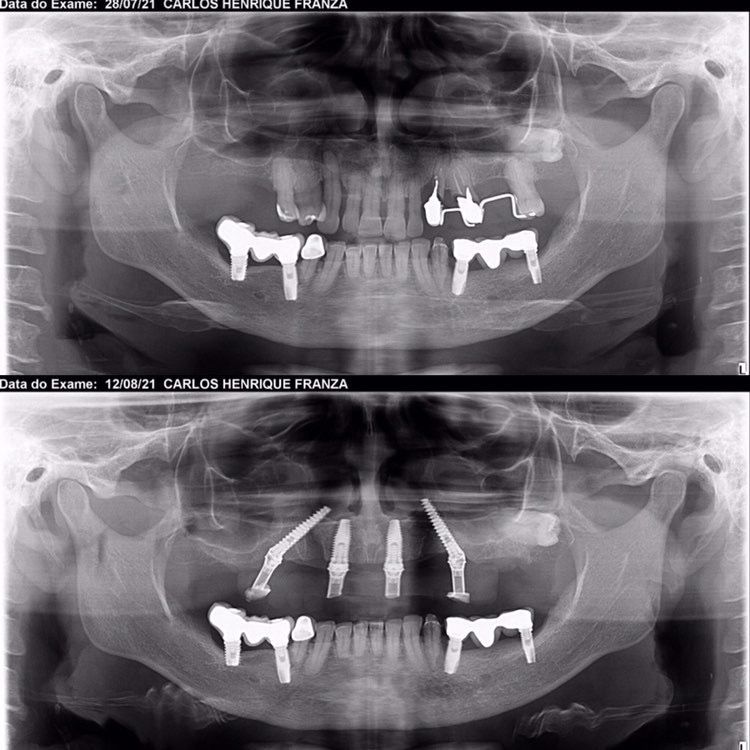

Case 005 Case: Técnica de ancoragem esquelética “All on Four STD” pelo Dr. Carlos Franza

Formado há 20 anos, o experiente Dr. Carlos Franza tem como foco de trabalho casos complexos de reabilitação total.

Atua no estado de São Paulo desde 2002 na área da implantodontia e Bucomaxilo, buscando sempre parcerias e interações de grandes profissionais da área no desenvolvimento e operacionalidade de novas técnicas buscando acima de tudo, satisfação dos pacientes.